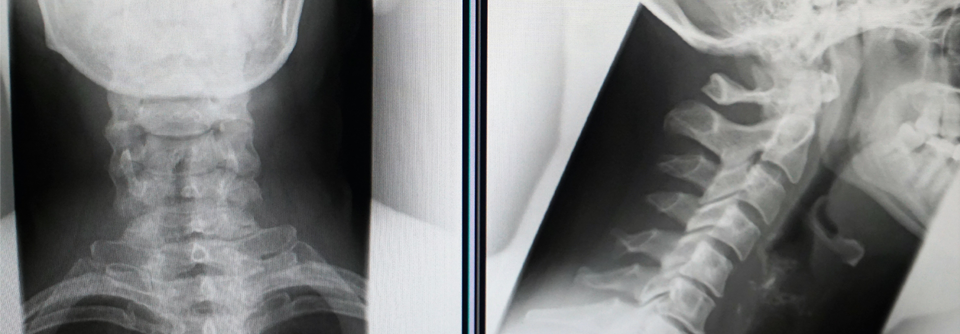

Risikofaktoren für Wirbelfrakturen durch eine Radiatio sind u.a. Alter, Strahlendosis und Knochendichte. Risikofaktoren für Wirbelfrakturen durch eine Radiatio sind u.a. Alter, Strahlendosis und Knochendichte. © Alex Tihonov – stock.adobe.com